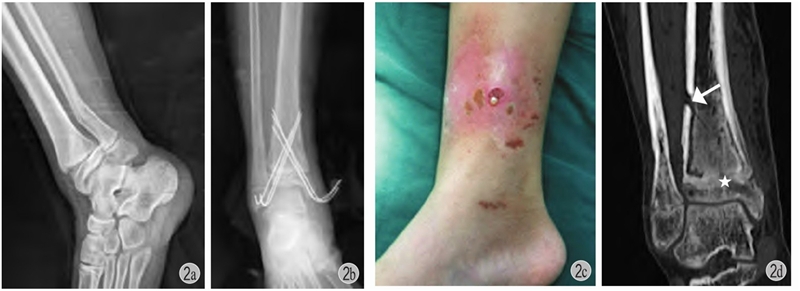

(1)虽然光滑克氏针可以贯穿骺板,但不等于不会给骺板带来损伤,只是损伤小未引起宏观的发育障碍。如果反复贯穿骺板操作,会导致局部骨桥形成、骺板早闭,引起肢体短缩和(或)成角畸形(图2)。(2)出针点如果过于集中,克氏针钻入时产热会引起局部骨坏死 (图2)。

图2 患儿 男 11岁

a:右胫骨远端骨骺骨折(Salter-HarrisⅡ型)合并腓骨远端骨折;b:闭合复位,胫骨远端6枚克氏针贯通骺板固定;c:术后4个月见右小腿远端红肿,流脓;d:愈合后出现胫骨远端骺板早闭(星号)+局部皮质骨坏死(箭头)+慢性骨髓炎形成